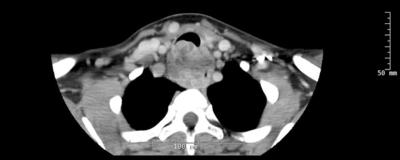

The patient had a large bulky tumor encasing the cervical esophagus, positive for low grade adenoid cystic cancer, which invaded the posterior tracheal wall over the length of 6 cm. The tumor was located 2 cm below the vocal cords and 3 cm above the carina.

CT scan of the tumor